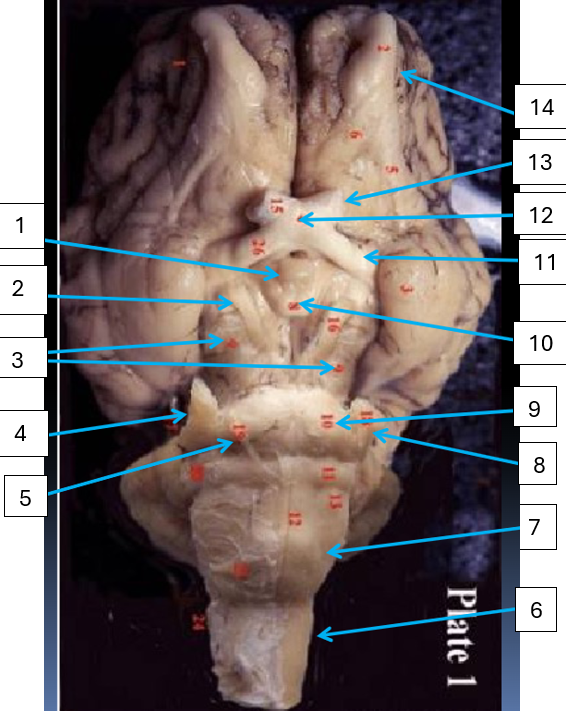

1

infundibulum, connects hypothalamus to pituitary gland

2

oculomotor nerve, CN3, eye muscle control

3

cerebral peduncle, connects cerebrum to pons

4

trigeminal nerve, CN5, motor control of jaw muscles

5

abducens nerve, CN6, eye muscle control

6

spinal cord, reflex area

7

medulla oblongata, controls vital autonomic functions like heart rate

8

9

pons, connects brain with lower CNS centers

10

mammillary body, relay station for olfaction

11

optic tract, carries visual information from optic chiasma to visual cortex

12

optic chiasma, area where medial portion of optic nerves cross

13

optic nerve, CN2, vision

14

olfactory bulb, houses synpases of olfactory nerve fibers, CN1, olfaction